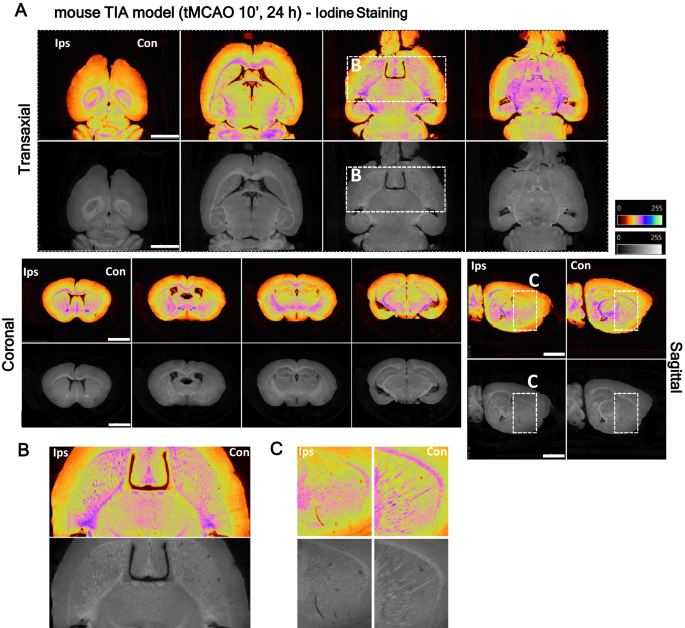

Additionally, striatum myelinated fiber degeneration was perceptible in the transient ischemic attack (TIA) model, with brains stained with either osmium or iodine, and corresponds to the total lesion and core/penumbra areas identified by micro-CT (Fig. 3, Supplementary Fig. 4, respectively-white stripes, pink/purple color; Supplementary Video 2). Micro-CT imaging allowed the detection of small lesions in myelinated fibres after the mouse TIA model. The contrast conferred by the stains (Osmium- Supplementary Fig. 4, Supplementary Video 2; Iodine—Fig. 3) enabled the visualization of white matter loss in the affected hemisphere’s striatum, when compared to the contralateral hemisphere, after 24 h of reperfusion. The white matter fiber tracts loss was uniform throughout the striatum, and not localized to regions within the ischemic injury, since this model does not present a visible infarct area (Fig. 3 and Supplementary Fig. 4). Thus, both osmium and iodine ex-vivo stained brains show clear stroke consequence demarcation that parallels histopathological-defined ischemia.

Identification of striatum white fiber degeneration in transient ischemic attack (TIA) mouse model lesions by high-resolution micro-CT imaging. (A) Virtual slices (~ 4 µm voxels) at different orientations from micro-CT scan of a TIA brain stained with inorganic iodine, showing striatum white fiber degeneration induced by 10 min MCA occlusion. (B,C) The below panel shows lesion detail in the transaxial and sagittal plane. Scale bar: 2 mm.